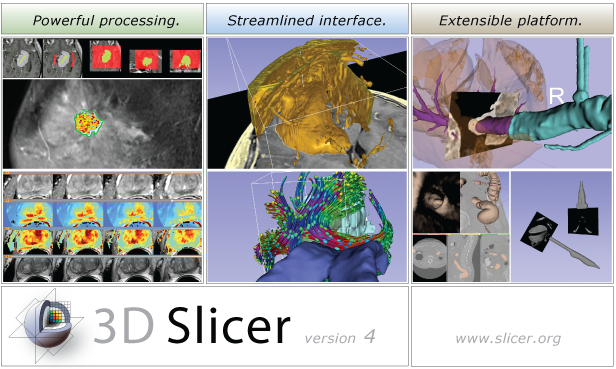

The community of Slicer developers is proud to announce the release of Slicer 4.0.

- Slicer 4.0 includes a major overhaul of the user interface, improved and simplified workflows for major tasks, simplified procedures for developers, and improved Python support.

Slicer is a community platform created for the purpose of subject specific image analysis and visualization.

- Multi-modality imaging including, MRI, CT, US, nuclear medicine, and microscopy

- Multi organ from head to toe

- Expandable and interfaced to multiple toolkits

Slicer Highlights